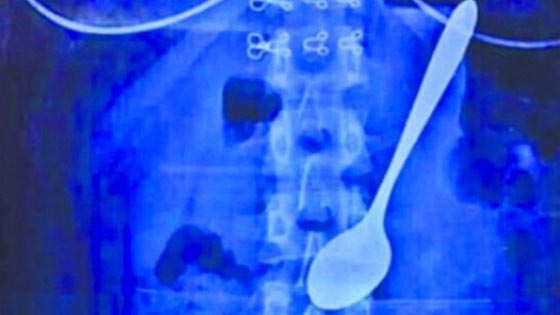

دخلت طالبة جامعة صينية من مدينة ووهان في مقاطعة خوباي المستشفى بعد أن ابتلعت بالصدفة ملعقة معدنية طولها 14 سنتيمترا. كانت هذه الشابة تأكل بملعقة من كأس مملوءة بالآيسكريم وهي في طريقها إلى السكن الطلابي، وفي هذا الوقت دفعها أحد الطلاب من الخلف عندما كانت الملعقة في فمها ، الأمر الذي جعلها تبتلع الملعقة مع الآيسكريم من دون إرادتها.

حسب قول الفتاة فإنها لم تعتبر ذلك الحادث خطرا ولم تراجع طبيبا في بداية الأمر. لكن بعد الاطلاع على مضاعفات حوادث مماثلة في الإنترنت قررت الذهاب إلى المستشفى. انتشل الأطباء الملعقة من معدة الطالبة بنجاح حيث لم تستغرق العملية أكثر من عشر دقائق دون أن تسبب أي إصابات داخلية.